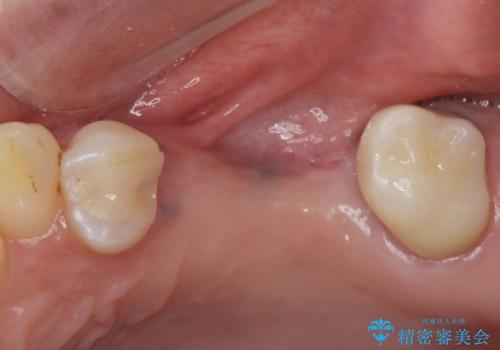

左上の小臼歯、大臼歯が欠損しているため。インプラントのご案内をさせてもらったところ外科的な処置は行いたくないとの事でしたので

部分入れ歯のご案内をしました。なるべく銀は見えたくないとの希望により保険の入れ歯ではなく自費の入れ歯(ノンクラスプデンチャー)を作製しました。

ノンクラスプデンチャーは保険の入れ歯に比べて異物感が少なく、またメタルの部分も少ないので目立ちません。